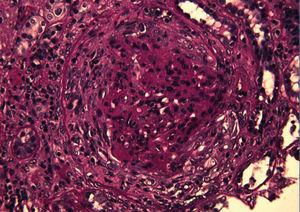

Figure 2. PAS stain shows a fibrocellular crescent in the urinary space that compresses the residual glomerulus and its tuft (PAS, x 400)